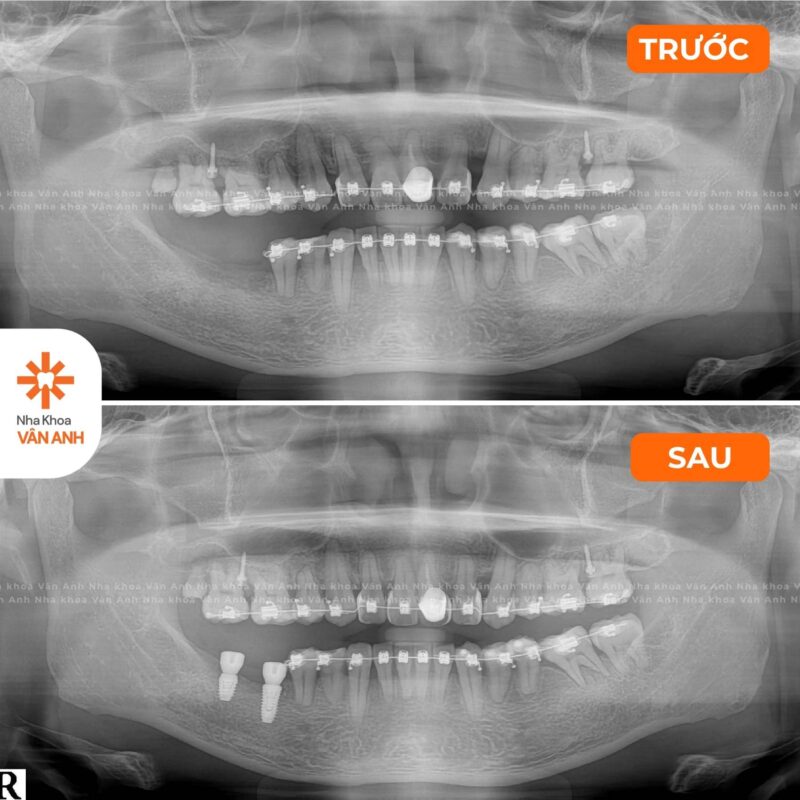

Lĩnh vực chuyên sâu: Phục Hình – Tiểu Phẫu

- Chứng chỉ Cắm Ghép Implant Nha Khoa – Viện Đào tạo Răng Hàm Mặt, Đại học Y Hà Nội.

- Chứng nhận đào tạo Cấy ghép implant Nha khoa nâng cao: Implant tức thì và Implant vùng thẩm mỹ – Viện Đào tạo Răng Hàm Mặt, Đại học Y Hà Nội.

- Chứng nhận đào tạo Nâng xoang GBR – Dentium Academy